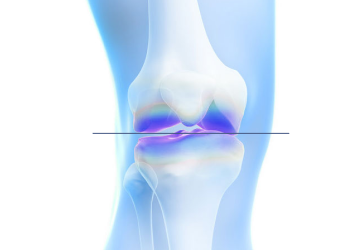

근위경골 절골술 교정 후

수술 전 환자의 상태

수술 후 1년